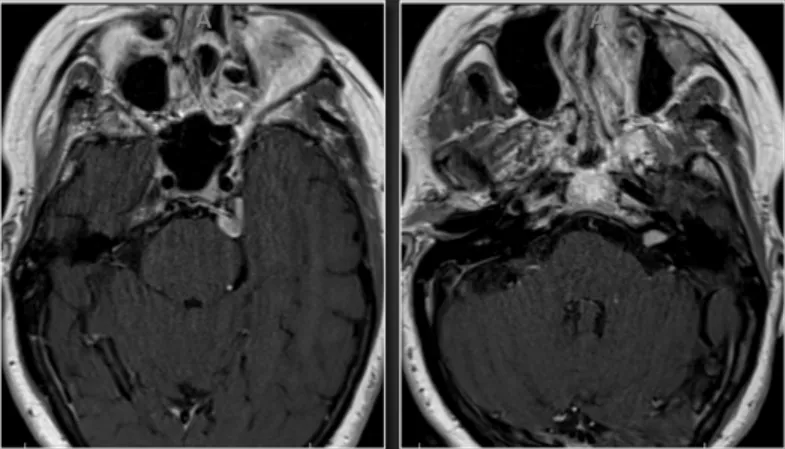

手术方案与体位的确定基于两处病变均引发症状,因此选择单一手术入路实施同期切除。采用中颅窝入路进行听力保留手术,并同期行岩骨前部切除以处理脑膜瘤。患者体位取侧卧位。中颅窝开颅、内听道磨除及岩骨前部切除操作中,沿颧颧弓根中心掀起4×4厘米骨瓣,识别棘孔后结扎脑膜中动脉。随后继续硬膜外解剖,定位弓状隆起及岩浅大神经(GSPN)。通过中颅窝入路磨开内听道,并保持硬脑膜完整性。为切除前庭神经鞘瘤,对内听道实施270°骨性开放。接着进行岩骨前部切除,磨除岩尖骨质。岩尖脑膜瘤切除步骤包括切开梅克尔腔表面硬脑膜,识别三叉神经根。在岩尖区域切开硬脑膜后,可见脑膜瘤向梅克尔腔延伸。完整切除脑膜瘤附着处硬脑膜,经硬膜开口分离肿瘤,使三叉神经根全程显露。前庭神经鞘瘤切除在脑膜瘤切除后进行,转向内听道处理前庭神经鞘瘤。术中持续监测听觉脑干诱发电位(ABR)。可见面神经位于肿瘤表面区域,通过充分磨除骨质实现肿瘤完整分离。在面神经表面缓慢分离肿瘤并行瘤内减容,清晰显示鞘瘤与神经界面。使用显微剥离器将肿瘤从其后方耳蜗神经区域抬起。切除鞘瘤后测试面神经功能,ABR反应保存完好。关颅步骤包括使用骨蜡封闭开放气房,以纤维蛋白胶复合脂肪组织填塞术腔。采用Medpor人工材料行颅骨成形术修复骨瓣,分层缝合头皮。术后影像与临床病程显示,影像学检查证实两处病变均获全切。患者术后出现一过性左侧外展神经麻痹,6周后完全恢复,听力保存完好。

手术方案与体位的选择鉴于两处病变均引起症状,决定通过单一手术入路完成同期切除。利用中颅窝入路实施听力保留手术,并同期进行岩骨前部切除以切除脑膜瘤。患者取侧卧位。中颅窝开颅、内听道磨除及岩骨前部切除过程中,沿颧颧弓根中心掀起4×4厘米骨瓣,识别棘孔并结扎脑膜中动脉。继续硬膜外解剖,定位弓状隆起及岩浅大神经(GSPN)。经中颅窝入路磨开内听道,维持硬脑膜完整性。为切除前庭神经鞘瘤,对内听道完成270°骨性开放。随后行岩骨前部切除,磨除岩尖骨质。岩尖脑膜瘤切除时,切开梅克尔腔表面硬脑膜,识别三叉神经根。在岩尖区域切开硬脑膜,可见脑膜瘤向梅克尔腔延伸。完整切除脑膜瘤附着处硬脑膜,经硬膜开口分离肿瘤,三叉神经根全程显露。前庭神经鞘瘤切除在脑膜瘤切除后开展,转向内听道切除前庭神经鞘瘤。术中持续监测听觉脑干诱发电位(ABR)。可见面神经位于肿瘤表面区域,通过充分磨除骨质实现肿瘤完整分离。在面神经表面缓慢分离肿瘤并行瘤内减容,清晰显示鞘瘤与神经界面。使用显微剥离器将肿瘤从其后方耳蜗神经区域抬起。切除鞘瘤后测试面神经功能,ABR反应保存完好。关颅操作包括使用骨蜡封闭开放气房,以纤维蛋白胶复合脂肪组织填塞术腔。采用Medpor人工材料行颅骨成形术修复骨瓣,分层缝合头皮。术后影像与临床病程中,影像学证实两处病变均获全切。患者术后出现一过性左侧外展神经麻痹,6周后完全恢复,听力保存完好。